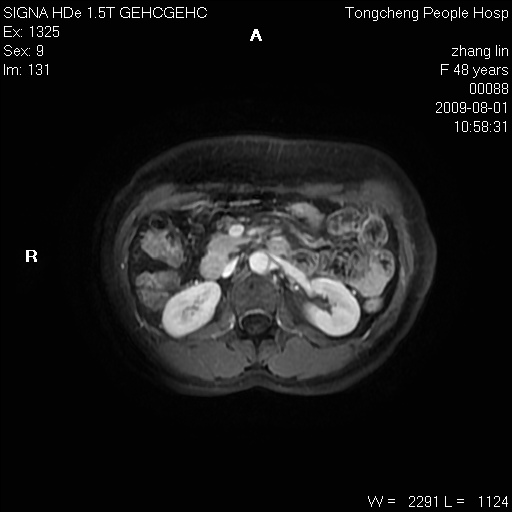

女,48岁。健康体检,彩超发现右肾占位性病变。平素健康。

临床诊断:右肾占位性病变,性质待定(囊肿?肿瘤?)。

上中腹部mr平扫+增强扫描,图像如下:

右肾上极见一类圆形病灶,t1wi呈等信号t2wi呈等高混杂信号,三期增强无强化,边界清---考虑囊肿出血。

同反相位均表现为等信号,病变无强化,考虑含蛋白的囊肿可能,弥散加权相或许有些帮助,

慢性胆囊炎